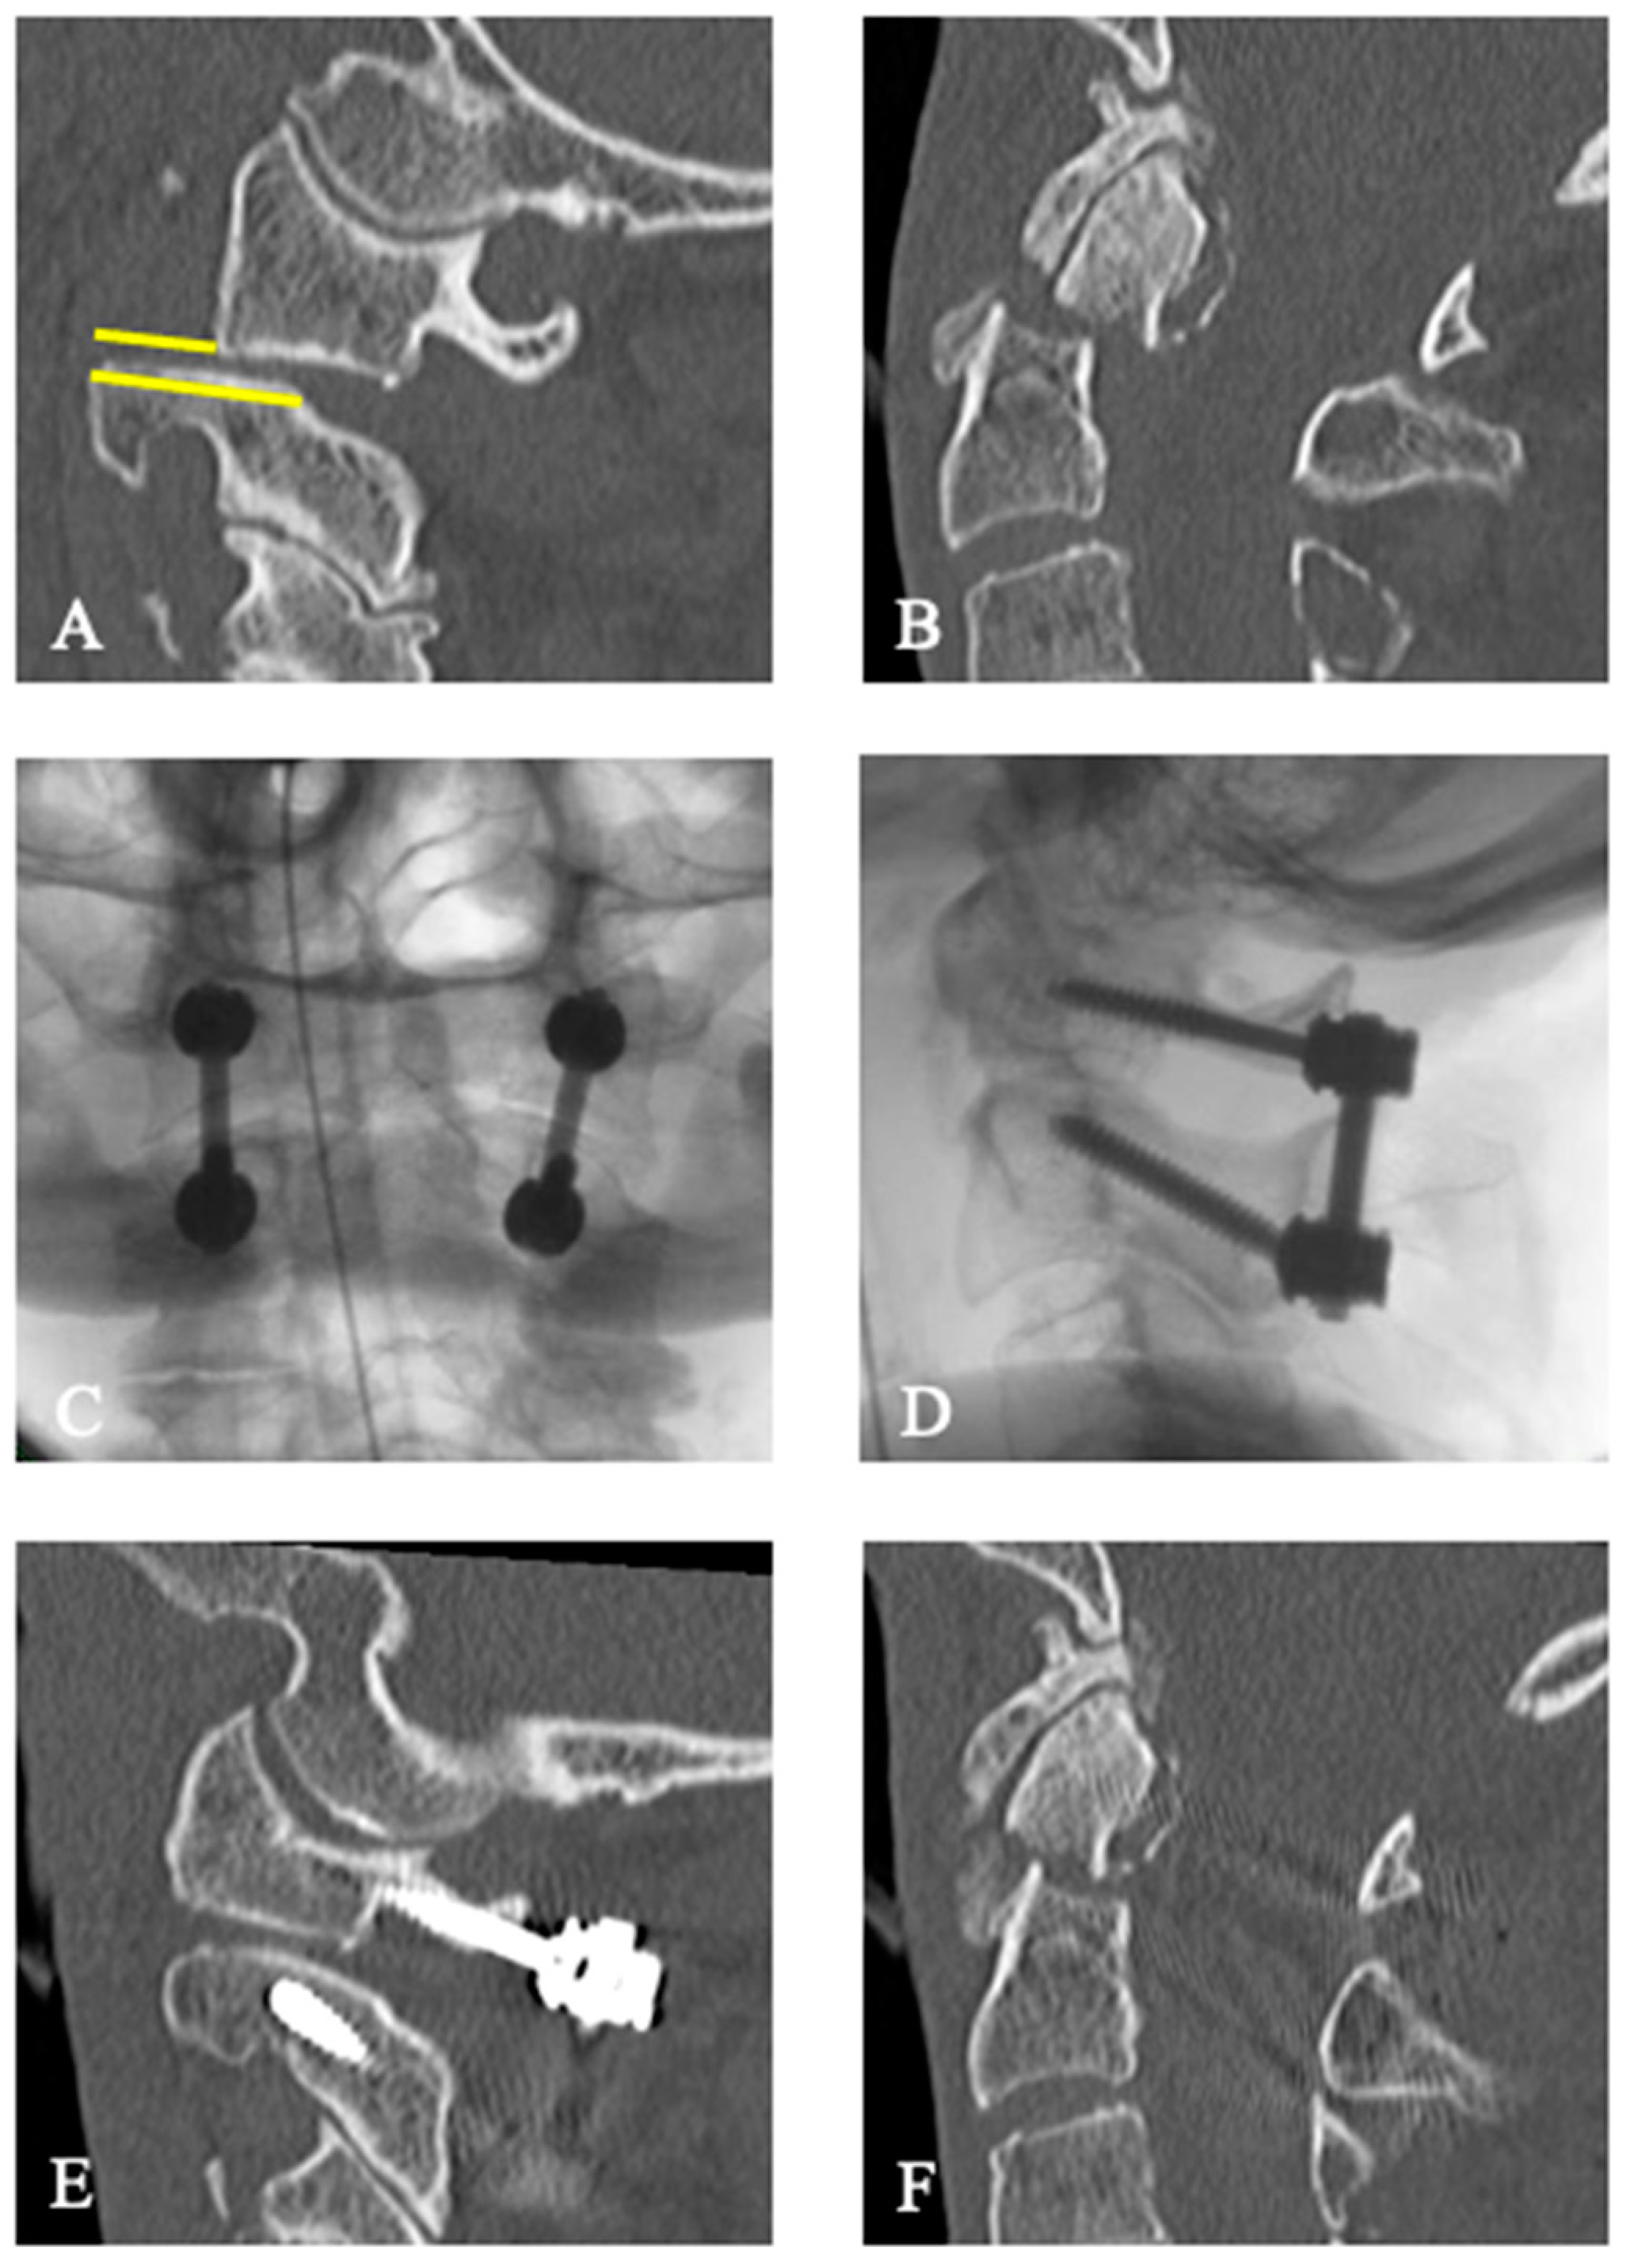

3.2. Treatment